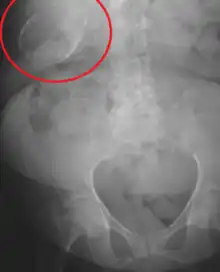

Porcelain gallbladder on X-ray

Porcelain gallbladder

Porcelain gallbladder is a calcification of the gallbladder believed to be brought on by excessive gallstones, although the exact cause is not clear. As with gallstone disease in general, this condition occurs mostly in overweight female patients of middle age. It is a morphological variant of chronic cholecystitis. Inflammatory scarring of the wall, combined with dystrophic calcification within the wall transforms the gallbladder into a porcelain-like vessel. Removal of the gallbladder (cholecystectomy) is the recommended treatment.

Abdominal radiography (X-ray), abdominal ultrasound or CT scan.